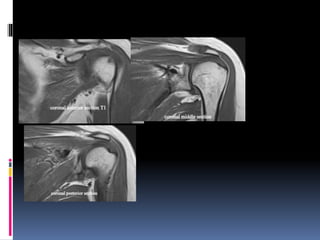

Shoulder MRI is done in a plane parallel to supraspinatus.

Coronal plane T1, T2, Fatsuppressed (STIR or PDFS)

Key section in shoulder

coronal image in the

middle third

Anterior coronal section

Posterior coronal section shoulder

Sagittal section

Anterior middle posterior

Coronal sections